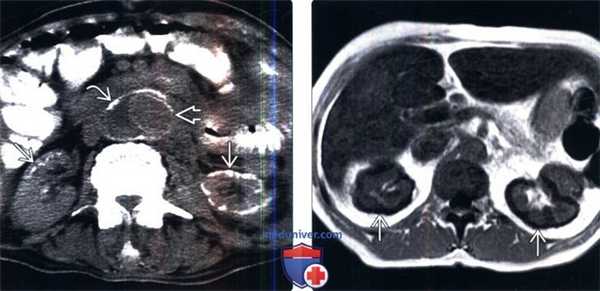

(Слева) КТ без контрастирования, аксиальная проекция: субкапсулярные кальцификаты обеих почек, что указывает на некроз коркового слоя почки, сопровождающийся шоком. Данные процессы вызваны разрывом аневризмы абдоминального отдела аорты. Обратите внимание на стенку аорты и эндографт.

(Справа) Градиентное эхо, Т1-ВИ, аксиальная проекция: у пациента с серповидноклеточной анемией выявлено противоположное изменение обычной кортико-медуллярной конфигурации с гипоинтенсивным корковым слоем по отношению к мозговому. Это может быть следствием отложения гемосидерина или кортикального некроза. Оба варианта возможны у пациентов с серповидноклеточной анемией.